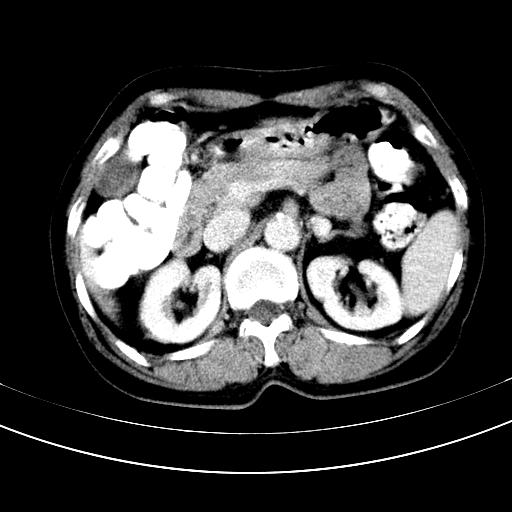

标题: CT12767:肝脏病变请会诊

补充强化片

胃内见充盈缺损,建议行胃镜病理检查,如果胃内无占位,则肝内考虑左叶、尾叶为包膜型肝癌,如有则考虑为转移瘤

胃内的充盈缺损,当时让患者俯卧位在扫描一下就 好了,当然最好是增强扫描,肝脏的病灶平扫很难定性,可以考虑是肝癌·血管瘤·转移瘤!

胃内见充盈缺损,建议行胃镜病理检查,如果胃内无占位,则肝内考虑左叶、尾叶为包膜型肝癌,如有则考虑为转移瘤,左侧肾上腺 明显增大,成结节改变,本人考虑转移瘤可能性大。

胃内的充盈缺损因胃壁不厚,我个人考虑为胃内残留物。肝左叶及尾叶病灶,我首先考虑血管瘤,其次为肝癌。(尾叶的更低密度区太规整)

肝脏左叶和尾叶均见略低密度影,尾叶病变内见坏死?其边界清晰,形态规整1血管瘤,2肝癌待排

胆囊内见一略高密度影,息肉?

1.肝左叶及尾叶占位建议增强2.肝硬化

肝脏左叶和尾叶均见略低密度影,尾叶病变内见坏死?其边界清晰,形态规整1血管瘤,2肝癌待排3建议增强。

胃内充盈缺损考虑为胃内存留物,肝左叶和尾状叶两个病灶,均为低密度,建议增强。

考虑:胃体小弯侧胃癌(或平滑肌瘤恶化或平滑肌肉瘤)伴肝转移,左侧肾上腺转移不除外.

胃内充盈缺损考虑为肿瘤,肝尾叶及左叶肿块考虑转移瘤

胃癌肝内转移及肾上腺转移。

不强化不好说!肝内像是血管瘤,胃底考虑间质瘤。脾静脉还有曲张的可能。本病例必须强化明确!

胃窦部占位伴肝及左肾上腺转移可能大,建议增强扫描。

肝脏左叶和尾叶均见略低密度影,尾叶病变内见坏死?其边界清晰,形态规整1血管瘤,2肝癌待排3建议增强或结合临床及超声与实验室检查